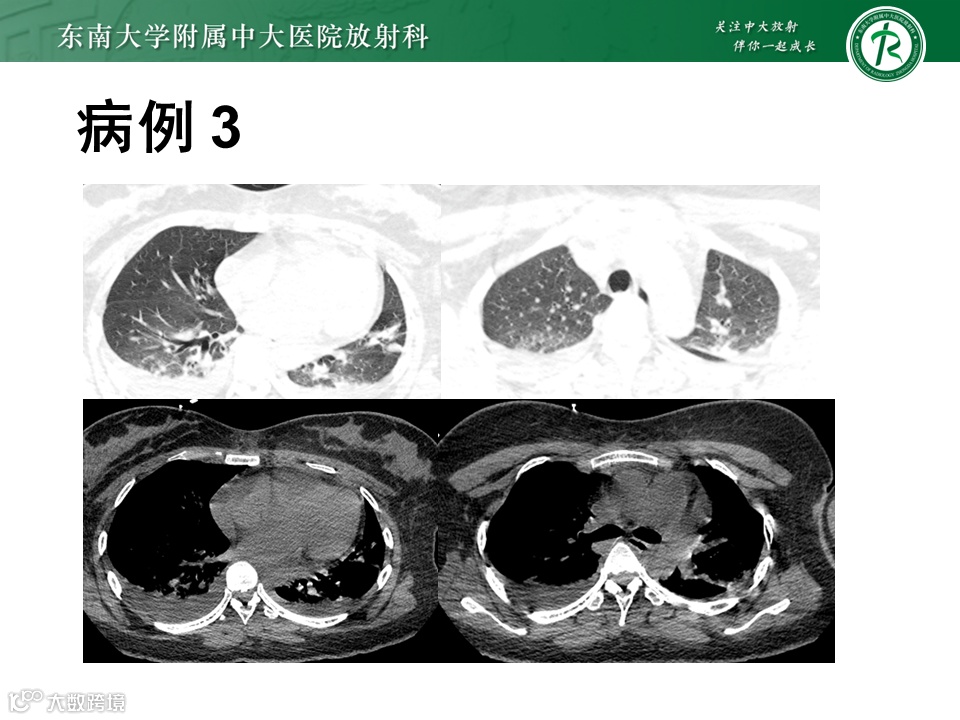

病例3:剖宫产后并发HELLP综合征